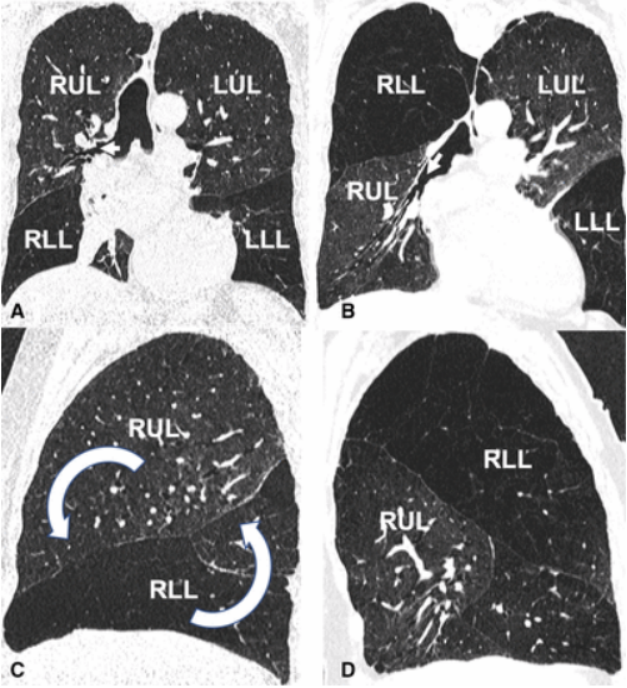

这“翻转”来的太突然,即使再次胸片检查也依旧如此。不得已行CT检查和三维渲染重建,见图3。胸部CT示右侧斜裂反转,中间支气管异常前行,肺血管旋转;右下肺动脉与中间支气管一起被拉向前行;右肺广泛实变,并伴有胸腔积液;外观显示右肺发生了180度扭转。

图3 胸部CT